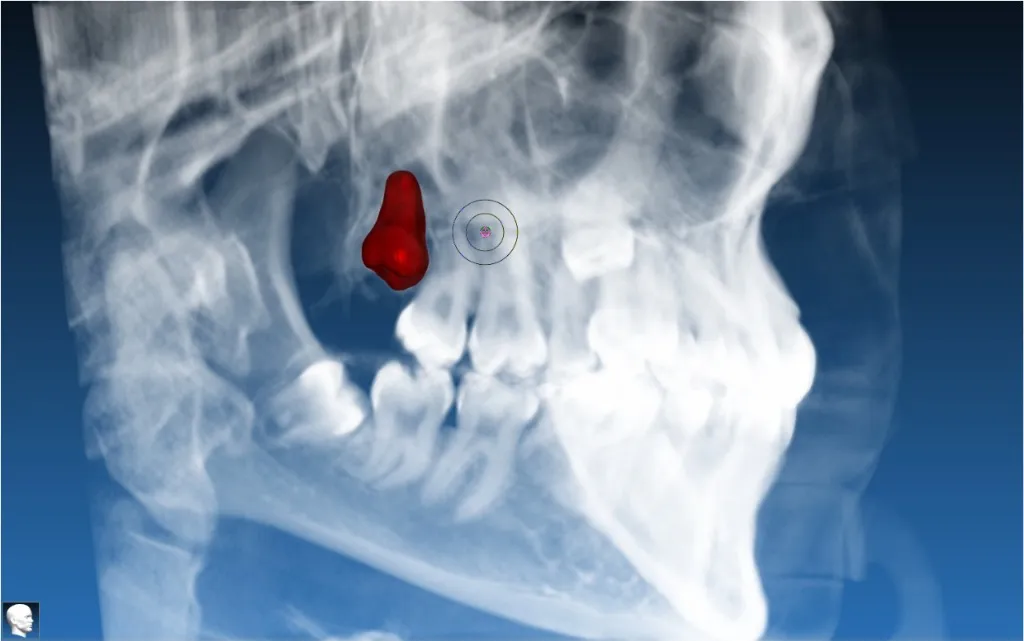

Single Implant with Bone Graft

Guided implant placement with simultaneous bone augmentation